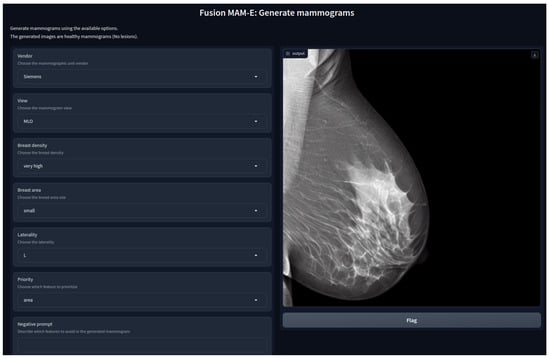

This work source code publication is the first implementation of SD for mammographic image generation and can be found at https://github.com/VICTORIA-project/mam-e (accessed on 21 March 2024), along with the pretrained weights at https://huggingface.co/Likalto4 (accessed on 21 March 2024). Additionally, graphical user interfaces for both synthesis tasks were designed, as shown in Figure 1, for easy-to-use image generation.

Figure 1.

Graphical user interface of MAM-E for generation of synthetic healthy mammograms.

We developed five GUIs, one for each of our main diffusion pipelines. Two were designed for the conditional generation of mammograms of the original Siemens and Hologic datasets separately, with their own prompt characteristics. Similarly, one pipeline was created for the combination of both datasets, and it is presented as an example in Figure 1. In these three cases, the personalization options are set fixed and the user can only pick from the available options. Nevertheless, we added the option of a negative prompt, which allows the user to further personalize the generation.